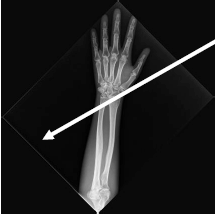

Observe a imagem a seguir:

Trata-se de uma radiografia do antebraço esquerdo. O osso à direita se chama